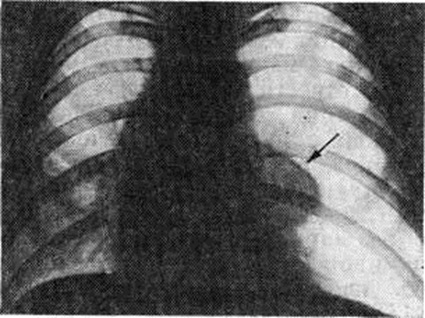

Для рентгенологического выявления пневмоторакса и его характера применяется многоосевое или полипозиционное исследование (смотри полный свод знаний). Рентгеноскопия грудной клетки в прямой проекции даёт ориентировочное представление о наличии Пневмоторакс и его характере и определяет выбор дополнительных методов исследования. Основным рентгенологическое признаком Пневмоторакс любой этиологии является участок просветления, лишённый лёгочного рисунка, расположенный по периферии лёгочного поля и отделённый от спавшегося лёгкого чёткой границей, соответствующей изображению висцеральной плевры (рисунок 1). При рентгенологическое исследовании выявляется связь плевральной полости с окружающей средой. Открытый травматический Пневмоторакс на вдохе характеризуется увеличением газового пузыря, дальнейшим спадением лёгкого, смещением органов средостения в здоровую сторону, смещением купола диафрагмы книзу. При закрытом травматическом Пневмоторакс рентгенологическое картина зависит главным образом от количества воздуха, скопившегося в плевральной полости, и связанного с этим внутриплеврального давления. Различают три типа закрытого Пневмоторакс: с давлением ниже атмосферного, выше и равным ему. При давлении ниже атмосферного количество воздуха в плевральной полости невелико. Лёгкое коллабировано незначительно, на вдохе оно увеличивается в объёме, на выдохе — спадается. При давлении выше атмосферного лёгкое резко коллабировано, его дыхательные экскурсии едва заметны, органы средостения смещены в здоровую сторону, диафрагма смещена книзу. Если давление при закрытом Пневмоторакс равно атмосферному, лёгкое коллабировано частично, дыхательные экскурсии сохранены, средостение смещено незначительно.

При клапанном (вентильном) Пневмоторакс спавшееся лёгкое не меняет своих размеров и конфигурации при дыхании, степень спадения лёгкого максимальная, средостение резко смещено в здоровую сторону, а на вдохе несколько перемещается в сторону поражения. Длительное нагнетание воздуха в плевральную полость при клапанном Пневмоторакс приводит к образованию напряжённого Пневмоторакс; при этом обнаруживается резкое смещение средостения в противоположную половину грудной клетки, диафрагма расположена низко, уплощена. Нередко определяется газ в мягких тканях грудной стенки. При тотальном Пневмоторакс газ занимает всю плевральную полость, тень средостения смещается в здоровую сторону (рисунок 2), купол диафрагмы опускается книзу.